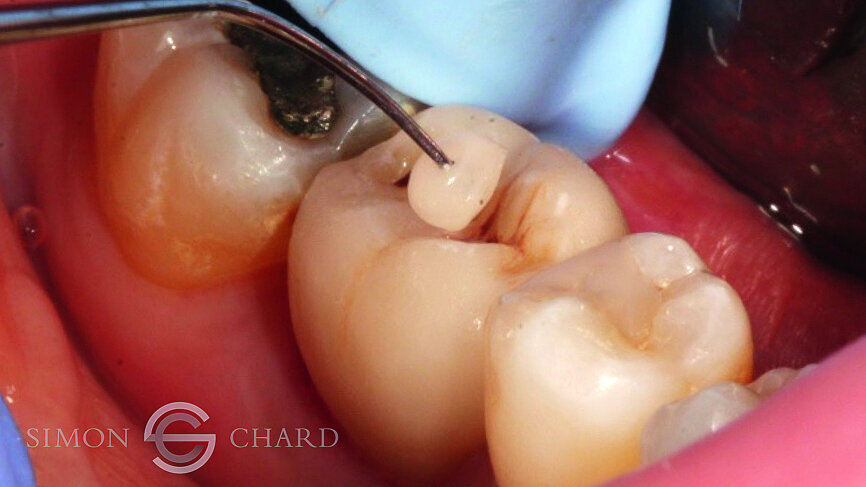

Following 3 months of integration, the patient attended the practice for the restoration of the implant with a definitive crown. During this period, the soft tissue had been given time to mature and a beautiful molar soft tissue profile had formed (Figs. 4 & 5).

Traditionally, capturing the detail of this soft tissue profile with analogue methods is complicated and time consuming; however, utilising a digital intraoral scan (CEREC Omnicam) a “gingival mask scan” can be taken to accurately replicate this soft tissue and use it to guide the subgingival emergence profile of the restoration (Fig. 6).

Following removal of the temporary crown, a TiBase was placed into the fixture head and a scan body used as a reference point for the scanning of the implant (Figs. 7 & 8).